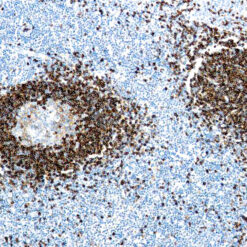

| Positive Control Tissue | Testis |